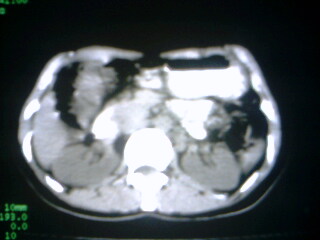

标题: CT9794:女 35Y 近两个月腹痛纳差明显消瘦 [打印本页]

标题: CT9794:女 35Y 近两个月腹痛纳差明显消瘦

在上几个层面肝脏有被病灶撑开的征像,病灶应该还是在肝上的,那就要考虑个猛的了,患然挺年轻,但对不住了,考虑肝癌

病人应该没有肝硬化病史,考虑胆囊癌可能性大,建议增强扫描除外肝腺瘤\\fnh等良性病变.

病变来自胆囊可能性大

增强,查afp。病灶象在肝内,若在胆囊内,肝内外胆管应有明显改变。

右肝癌。

巨大肿块。